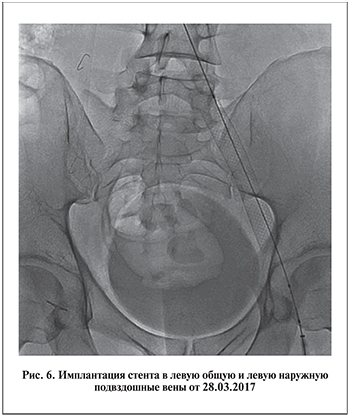

Через 3 мес. после ангиопластики и стентирования отмечено уменьшение максимального диаметра вен предстательной железы на 45%, по данным ТРУЗИ, и отсутствие антеградного кровотока при проведении цветного допплеровского ТРУЗИ простаты в покое и при пробе Вальсальвы (рис. 10). Результат сохранялся на протяжении 12 мес. наблюдения. В целом отмечено уменьшение венозного полнокровия простаты, которое сопровождалось уменьшением болевого синдрома и восстановлением половой функции. Причем данный результат, сохранявшийся в течение всего периода наблюдения, достигнут без проведения терапии болевого синдрома, хронического простатита и эректильной дисфункции. Через 6 мес. после операции отмечена редукция варикозно расширенных вен яичек и их придатков. По данным УЗИ органов мошонки, диаметр вен гроздевидных сплетений в клиностазе в спокойном состоянии был менее 2 мм. Рефлюкс отсутствовал как в клино-, так и в ортостазе при пробе Вальсальвы.